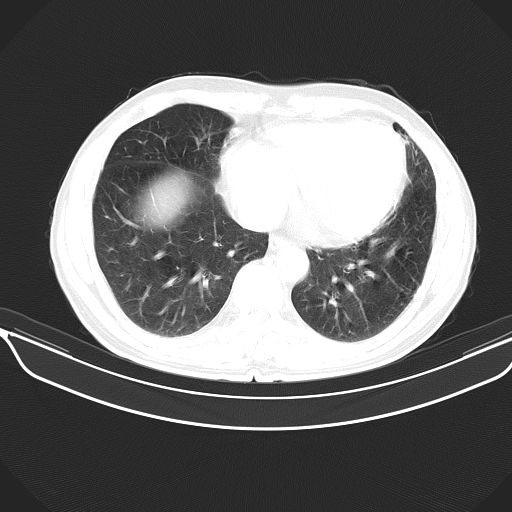

以下是引用心路寻觅在2010-3-1 10:23:00的发言:[br]1、考虑左肺上叶周围型肺癌[br]2、右上肺陈旧性病灶。[br][br][本贴已被 心路寻觅 于 2010-3-1 10:40:18 修改过]

以下是引用shuiyuan在2010-3-1 10:45:00的发言:[br]考虑左肺上叶中心型肺癌伴阻塞型炎症,邻近胸膜受侵。